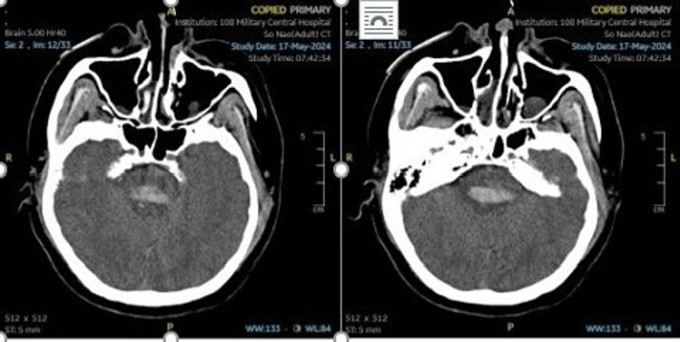

Tai biến xảy đến, người nhà đưa chị vào bệnh viện tuyến tỉnh cấp cứu, kết quả chụp cắt lớp vi tính sọ não thấy hình ảnh xuất huyết não, phù não. Ngọc được phẫu thuật mở sọ lấy máu tụ, sau đó chuyển đến Khoa Đột quỵ, Bệnh viện Trung ương Quân đội 108.

Hình chụp CT não một bệnh nhân đột quỵ do tăng huyết áp. Ảnh: Bệnh viện cung cấp

Hình ảnh chụp CT phát hiện bệnh nhân bị đột quỵ xuất huyết não do vỡ dị dạng mạch máu não. Bác sĩ cho biết dị dạng mạch máu não ở người trẻ do bẩm sinh. Theo thời gian, bất thường mạch ngày càng phát triển tăng lên về kích thước, dưới tác dụng của áp lực dòng máu, các thành mạch chỗ bất thường ngày càng mỏng đi, căng lên, đến một lúc nhất định sẽ vỡ. Đa phần người bệnh không có dấu hiệu điển hình, cảm thấy mình vẫn hoàn toàn khỏe mạnh. Kíp bác sĩ nút khối dị dạng mạch máu ngăn nguy cơ vỡ tái phát, song tình trạng còn nặng. Hiện chị Ngọc đã xuất viện, song bị di chứng liệt, trị liệu vật lý và hồi phục chức năng hàng ngày.